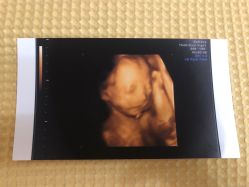

• -北京俪婴妇产医院(朝阳大悦城店)

相册

Niki 上传于 19-11-19 | 报错